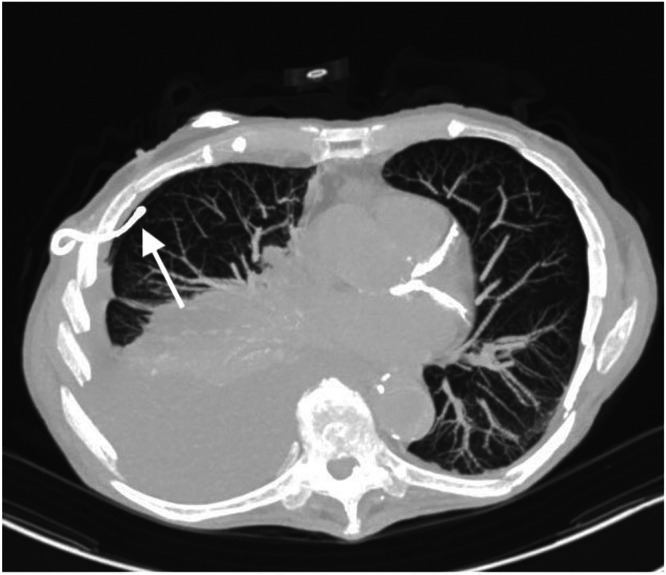

Results: In total, 151 out of 765 HGNS adverse events were related to the respiratory sensing lead, and of those, 75 were related to lead migration. There were seven events related to migration of the sensing lead into the pleural space, of which six cases underwent revision surgery (<1% of adverse events reported related to HGNS). Two cases noted pneumothorax due to sensing lead migration. We report two cases of sensing lead migration at our institution. Migration was demonstrated with serial imaging. These cases highlight the potential need for preoperative or intraoperative chest tube placement, based on the extent of migration, complications, and complexity.